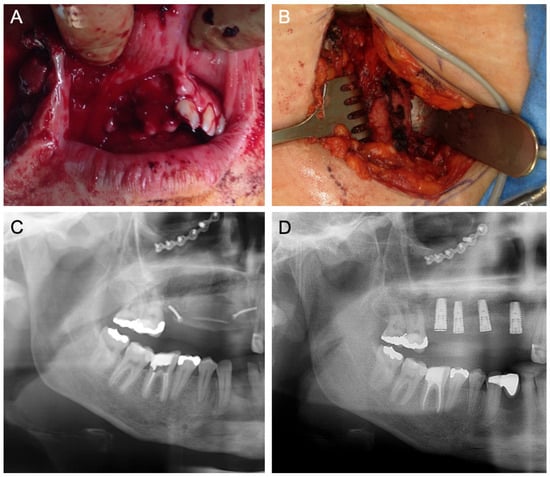

- ST—Prefabricated, processed allogeneic cortical bone plates (maxgraft® cortico; botiss), intraoperatively customized to fit the defect, filled with autogenous bone chips, allogeneic granules, and/or bovine BS (±hyaluronic acid), and fixed with titanium screws (Figure 7).